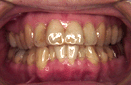

叢生

治療期間2年6ヶ月